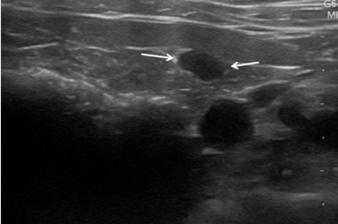

isovolumétrica (TRIV) acortado, 30 ms, y regurgitación mitral de hasta 4,6 m/s. En la ecocardiografía se observa también una masa hiperecoica bien definida de hasta 7 x 4,3 cm de diámetro en la base aórtica (Fig. 4) y un acúmulo de derrame pericárdico leve que no permite la pericardiocentesis. Además, se detecta un nódulo hiperecoico redondeado de 1,56 cm de diámetro en la válvula tricúspide (Fig. 5).

Figura 2. Ecocardiografía en corte paraesternal izquierdo eje largo, de 4 cámaras en la que se observa engrosamiento de la válvula mitral (flecha). Figura 3. Ecocardiografía en corte paraesternal derecho eje corto en base de corazón, visualizando ratio atrio izquierdo/aorta aumentado. Figura 4. Ecocardiografía en corte paraesternal izquierdo en base de corazón, en las que se observa la estructura hiperecoica y heterogénea junto a la aorta en un corte de la lesión transversal (A) y otro longitudinal (B). Compatible con neoplasia. A B Figura 5. Ecocardiografía en corte paraesternal izquierdo eje largo, optimizada para válvula tricúspide en la que se observa estructura hiperecoica.